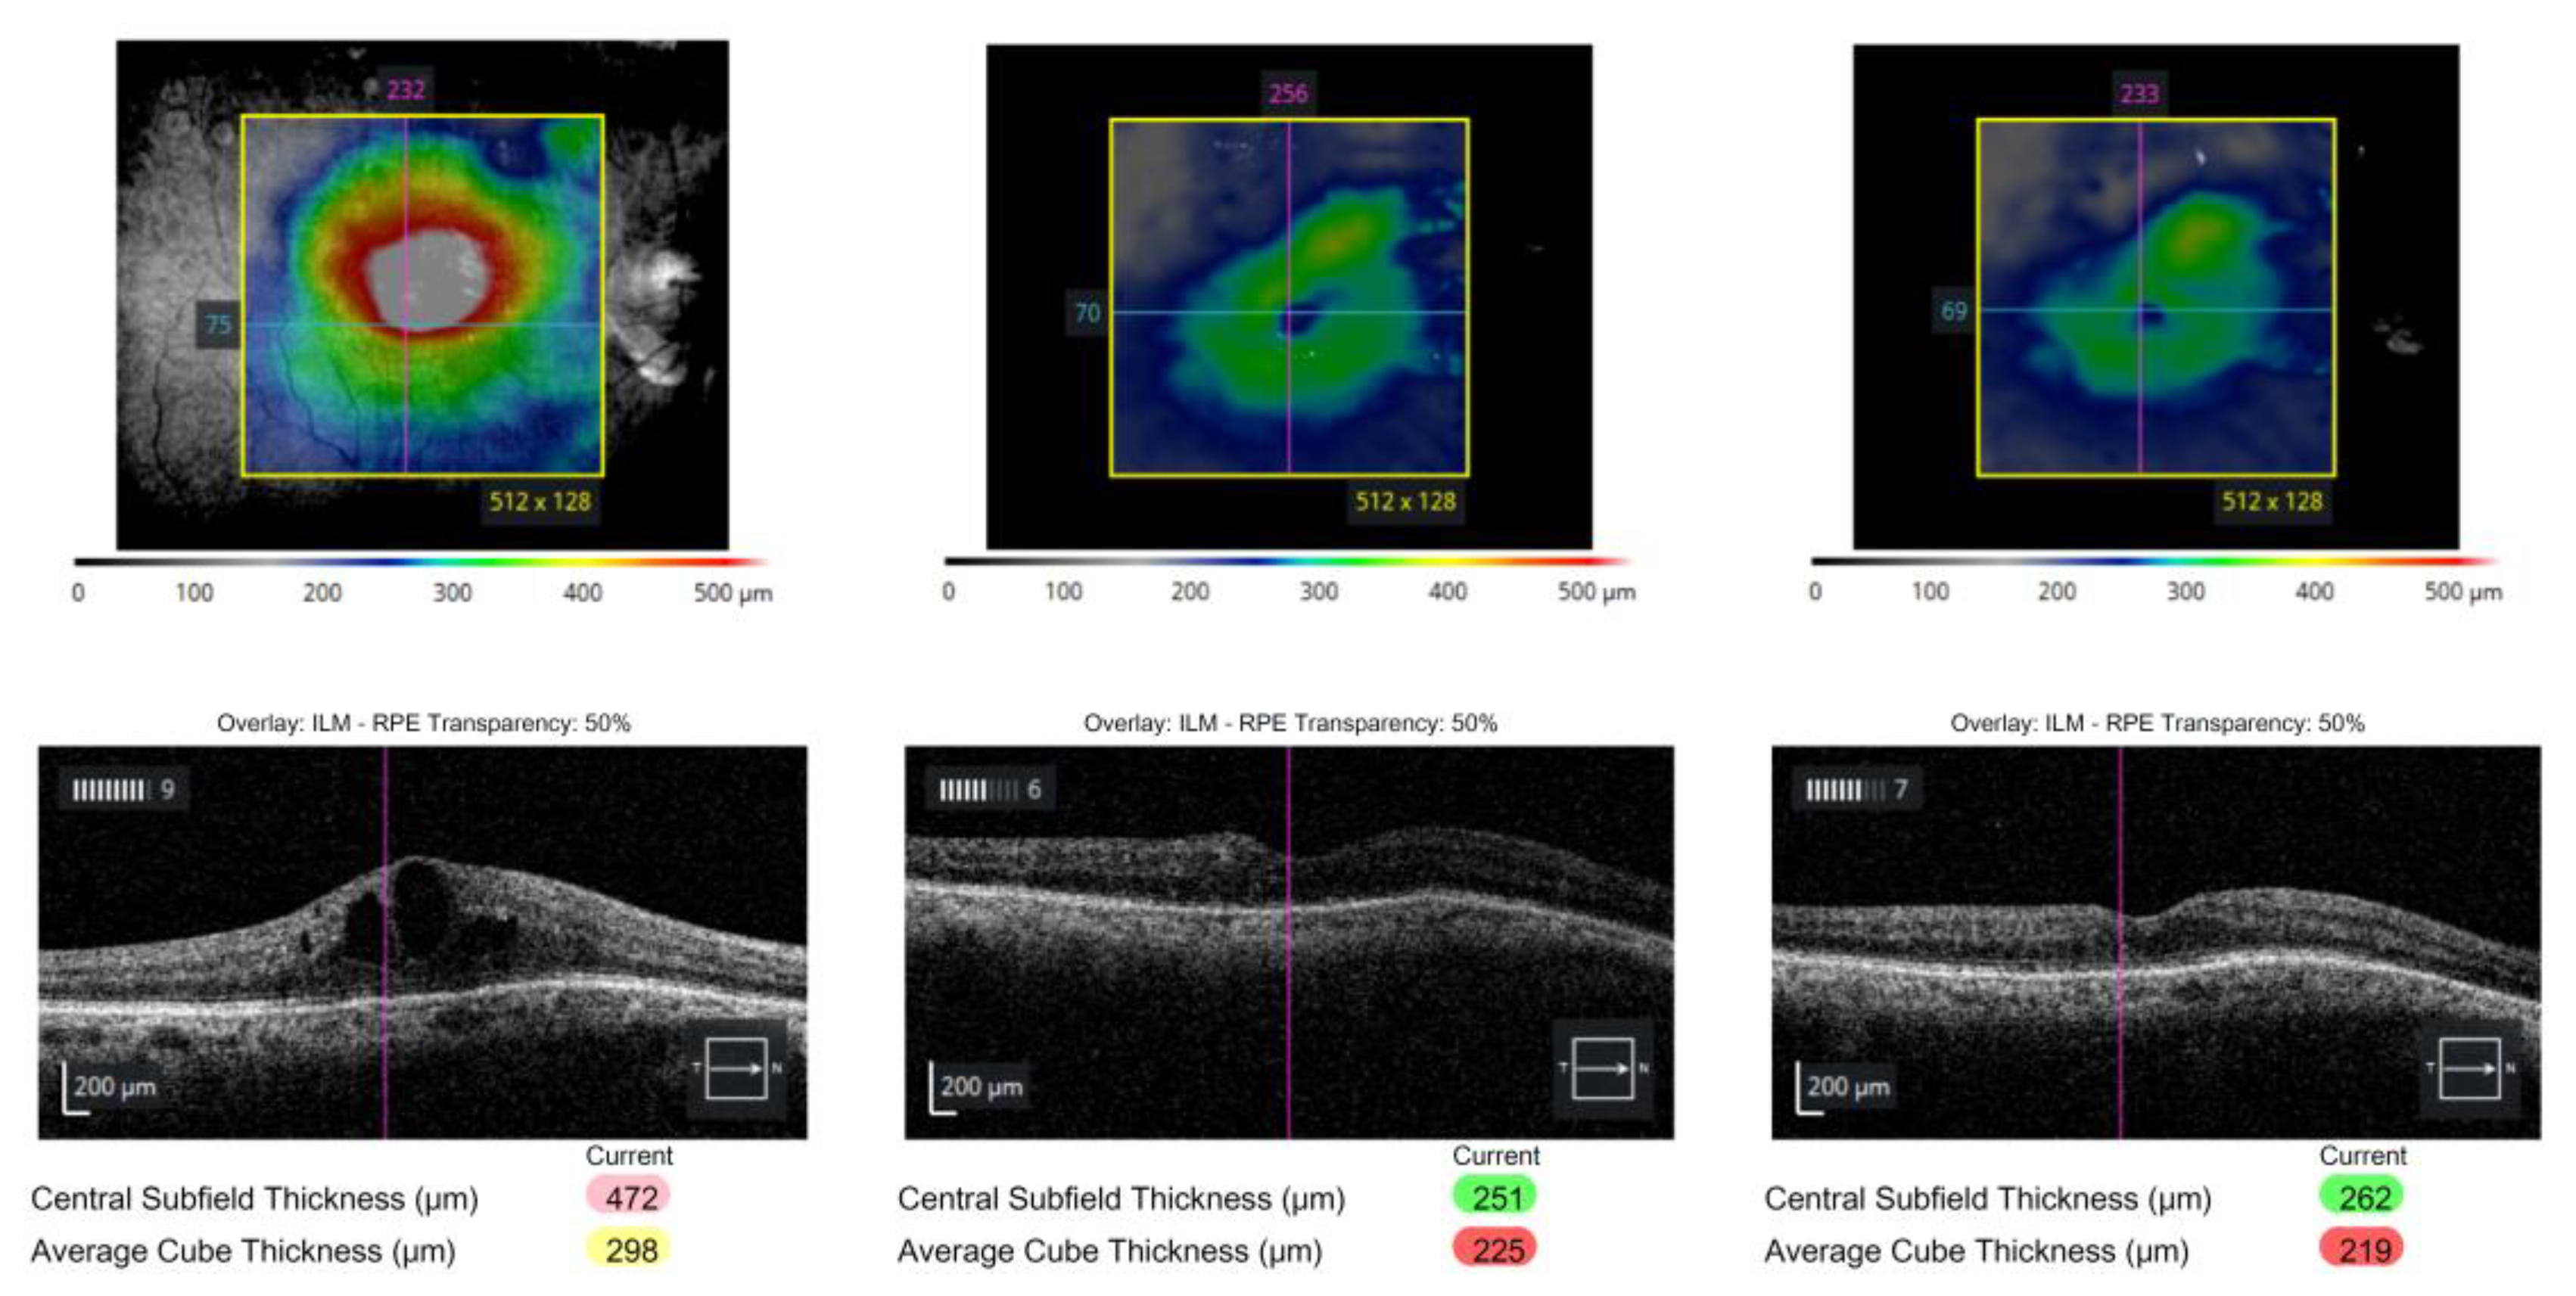

Prior to receiving the Ozurdex implant, his IOP had remained well-controlled at 17 mmHg on topical dorzolamide/timolol fixed combination (DTFC, Cosopt®, Santen Pharmaceutical Co., Ltd., Osaka, Japan) twice daily due to ocular hypertension. Within several months after implantation, the patient developed progressive ocular hypertension, with IOP rising to 26 mmHg despite triple topical therapy with DTFC, brimonidine (Alphagan®, Allergan, Abbvie company, Irvine, CA, USA), and bimatoprost (Lumigan®, Abbvie company, Irvine, CA, USA). The IOP subsequently increased further to 34 mmHg, and Humphrey 24-2 visual field testing revealed rapid stepwise deterioration (mean deviation, −7.56 dB, −10.20 dB, and −21.91 dB; visual field index, 87%, 82%, and 36% respectively). Fundus photography demonstrated a hyperemic optic disc and diffuse laser scars from prior focal photocoagulation. Optical coherence tomography (OCT) revealed progressive cystoid macular edema and structural thinning of the retinal nerve fiber layer (RNFL) and ganglion cell analysis, particularly in the superior and inferior arcuate regions, consistent with rapid glaucomatous progression (Figure 2).

Figure 2. Progressive functional and structural deterioration following intravitreal Ozurdex implantation. (left) Baseline wide-field fundus photograph, OCT, and Humphrey 24-2 visual field show moderate field loss (MD = –7.56 dB; VFI = 87%). (center) One month after Ozurdex®, despite partial reduction in macular edema, IOP increased to 26 mmHg, and the visual field further deteriorated (MD = –10.20 dB; VFI = 82%), accompanied by RNFL and GCA thinning on deviation maps. (right) At three months, IOP rose to 34 mmHg with marked worsening of visual field (MD = –21.91 dB; VFI = 36%) and diffuse loss of RNFL and GCA signal, consistent with steroid-induced glaucomatous progression.